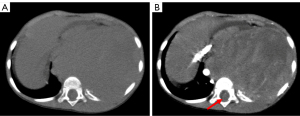

Two cases were found within the posterior mediastinal region, and both involved the erector spinae (Figure 1), with 1 tumor involving the spinal epidural. In 3 cases, the tumor was found within the mid-posterior mediastinal region. In one of these cases the tumor surrounded the esophagus and thoracic aorta; in the other case, the left lung was obviously disturbed by pushing and compression, and the heart and trachea were obviously displaced to the right, involving the erector spinae and spinal epidural (Figure 2). In 1 case, the tumor was found in the anterior, middle, and posterior mediastinal region, and it invaded the left hilum and left lung lobe. Here, the heart and trachea were significantly displaced to the left, and the left upper lobe was obviously disturbed by pushing pressure as in the other case. The maximum diameters for these cases were 3.8–16.0 cm, with an average of 10.0±5.0 cm.

The tumors were irregular ovals in 3 cases, irregular in 2 cases, and fusiform in 1 case, although in all 6 cases the tumor boundary was unclear. Varying degrees of necrosis and cystic degeneration were observed in all tumors, and calcification was observed in 2 tumors. One of these cases had cloud-like calcification (Figure 3) and the other case had speckle-like calcification. Hemorrhage within the tumor was seen in one case (Figure 4), and this tumor showed progressive and marked heterogeneous enhancement after contrast enhancement (Figures 2,4). Here, the adjacent structures were pushed or invaded to varying degrees. Patchy shadows were found in the lungs in 4 cases. Furthermore, adjacent ribs were invaded in one case (Figure 2), and the vertebral body was invaded in one case. Pleural effusion was seen in 4 cases, in a small amount in 3 of them, and in a large amount in the remaining one (Figure 3). In addition, one of these 4 was associated with pericardial effusion. Finally, 3 patients had extensive metastases to the pleura (Figure 3), and enlarged mediastinal lymph nodes were seen in 2 cases.